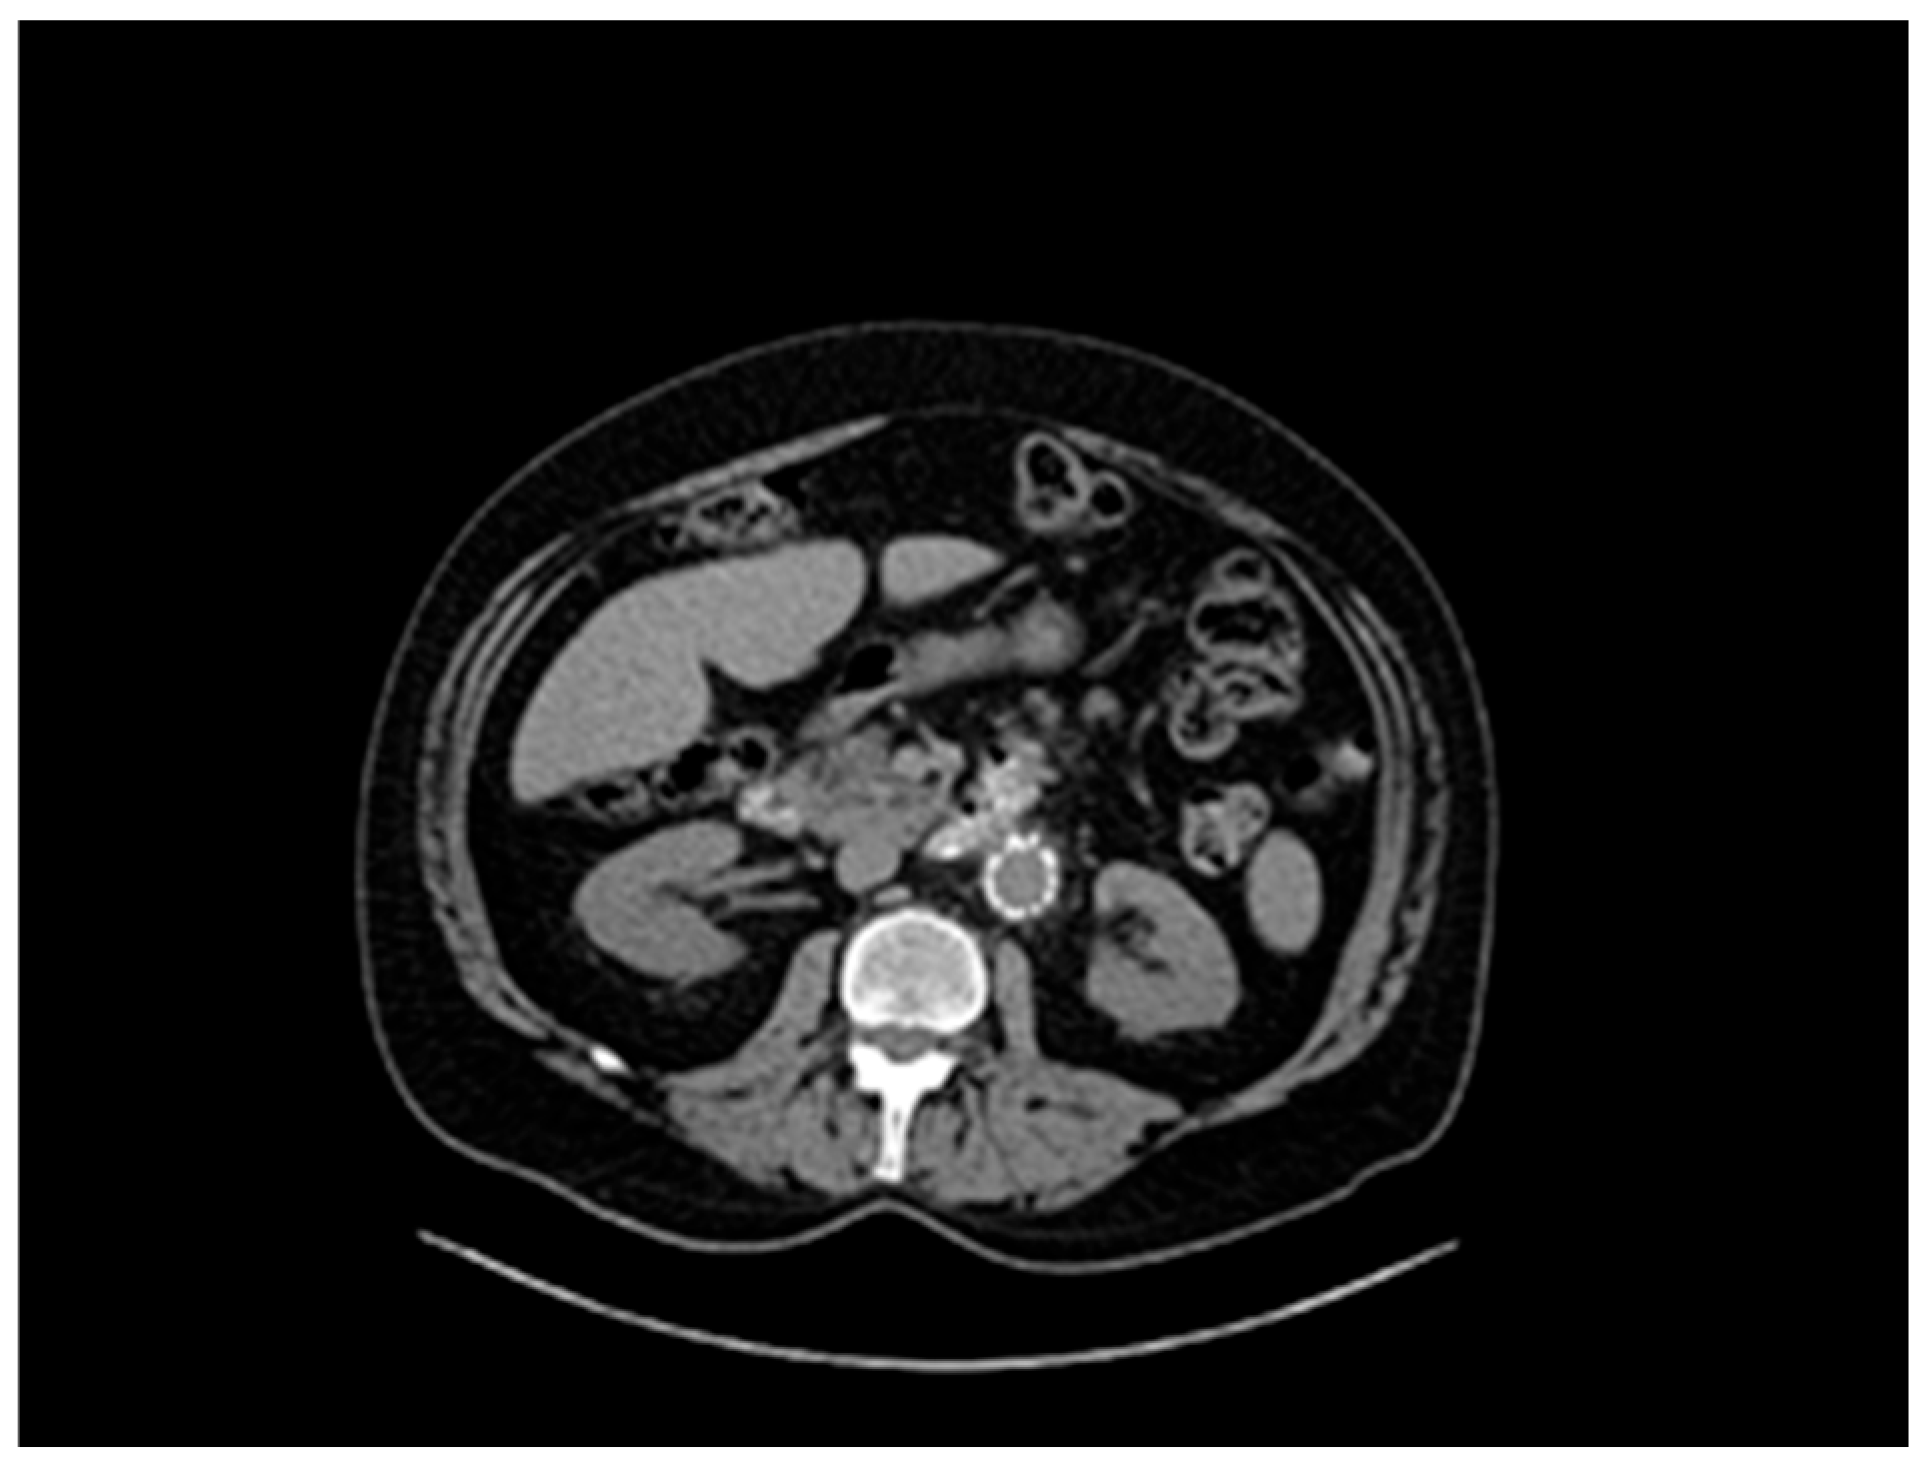

A 61-year-old patient with a history of probable Marfan syndrome was examined after referral from the treating physician because of hyperthyroidism. The tentative diagnosis of Marfan syndrome was set two decades ago based on the patient’s phenotype and a personal record of a Sinus of Valsalva aneurysm. The phenotype included a tall and lean statue, high-arched palate, crowded teeth, arachnodactyly, and divergent strabismus (Figure 1). The patient gave informed consent for the publication of his photo. The patient’s height was 188 cm, and his current weight was 88 kg. At the age of 49, a diagnosis of a 7 cm Sinus of Valsalva aneurysm was made (Figure 2), accompanied by concurrent grade 3 to 4 aortic valve insufficiency. The aortic aneurysm’s Z-score was 7.6, considering the patient’s sex, age, height, and weight. Previous surgical intervention involved an aortic valve replacement. Six years later, at the age of 55, the patient was hospitalized for an infrarenal abdominal aorta aneurysm measuring 4.9 cm, which was managed with endovascular repair and stent placement (Figure 3). Other medical history included an ischemic stroke in the right middle cerebral artery at age 56, attributed to insufficient anticoagulation in the context of a prosthetic aortic valve. The stroke did not result in any lasting neurological deficits. The patient did not present with cerebral aneurysms and had no history of arterial hypertension, hypercholesterolemia, diabetes mellitus, or active smoking.

Figure 3. Abdominal aorta stent graft.